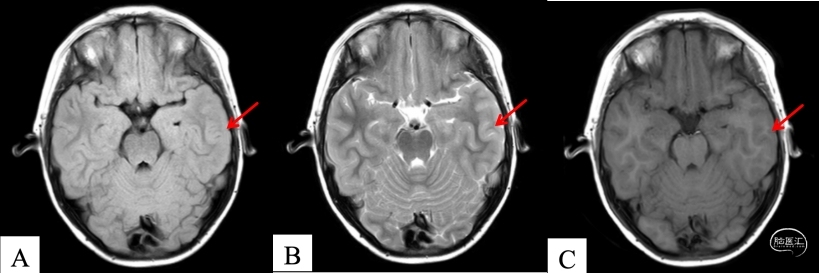

2.头部MR:左颞叶皮层灰白质交界不清,局灶性皮层发育不良可能性大(图3)

图3:头部MR可见左颞皮层灰白质交界不清(红色箭头指示)。